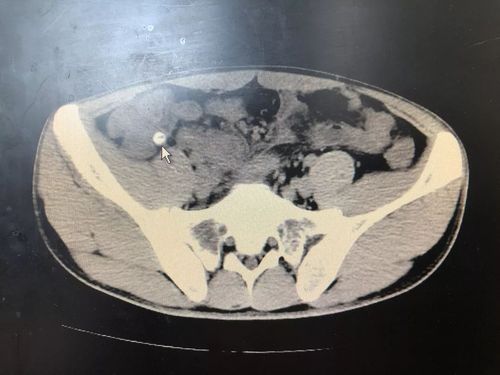

阑尾粪石ct

阑尾粪石ct,阑尾炎粪石图片 自愈

阑尾粪石ct图片

阑尾粪石ct图解图像

粪石ct图片

阑尾粪石影像图片